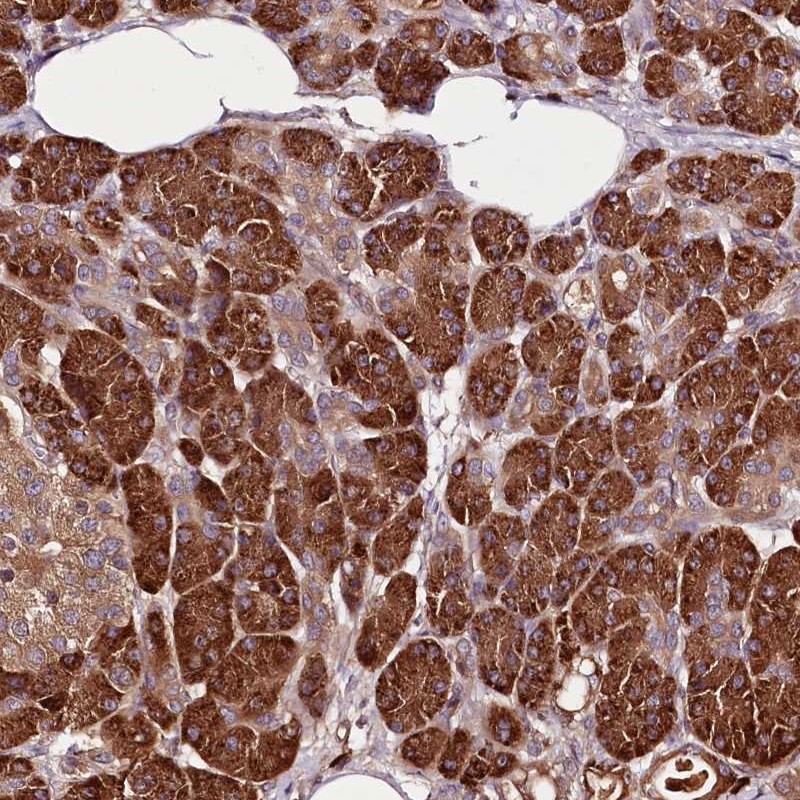

Immunohistochemical staining of human pancreas shows strong cytoplasmic positivity in exocrine glandular cells.